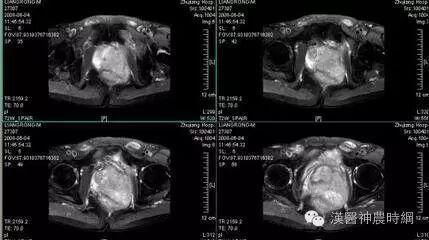

腺癌生长较快,病程较短。肿瘤呈浸润性生长,常与正常组织界限不清,活动度差,甚至固定。晚期可侵及皮肤、肌肉、神经、骨组织,可造成肿瘤表面溃疡、疼痛以及张口困难等症状。发生于腮腺者可与外耳道、颞骨以及下颌骨粘连固定,发生于颌下腺者可与口底、下颌骨固定。

(三)生物学特点 腺癌具有高度浸润和破坏性生长特征。腺癌易侵犯血管和淋巴管壁,而出现较多的血行及淋巴转移。